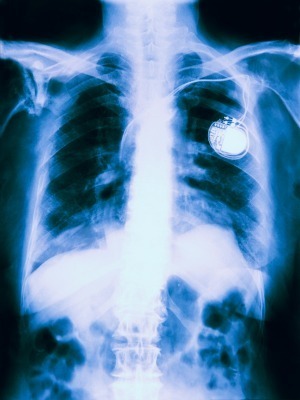

According to the complaint, on Sept. 30, 2013, Chessor was admitted to Memorial Hospital for a generator change to his pacemaker. The suit says McPike performed the surgery but the treatment caused injuries.

The lawsuit states McPike ignored Chessor when the pacemaker started causing him pain, that the defendant failed to choose an appropriate site for the implantation, that the defendant failed to recognize the pacemaker was herniating out of the plaintiff's chest and that the defendant did not initiate appropriate treatment for all these issues.